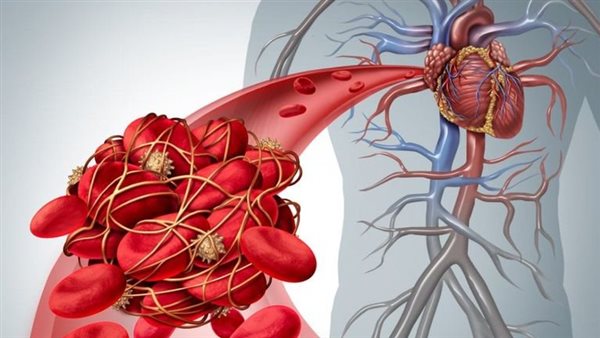

كشف الدكتور هيثم رمضان، استشاري أمراض القلب والأوعية الدموية، عن أعراض الجلطة الرئوية عند الشباب، فهي عبارة عن وجود جلطة تحدث في أحد الأوعية الدموية، وعادة ما تكون في الذارع أو الساق، ثم تنتقل إلى شرايين الرئة، مما تؤدي إلى منع تدفق الدم إلى الرئتين ومن ثم يصاب الشخص بانخفاض مستوى الاكسجين، مما يؤدي إلى تلف جزء من الرئة.